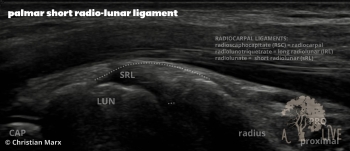

carpal ligaments